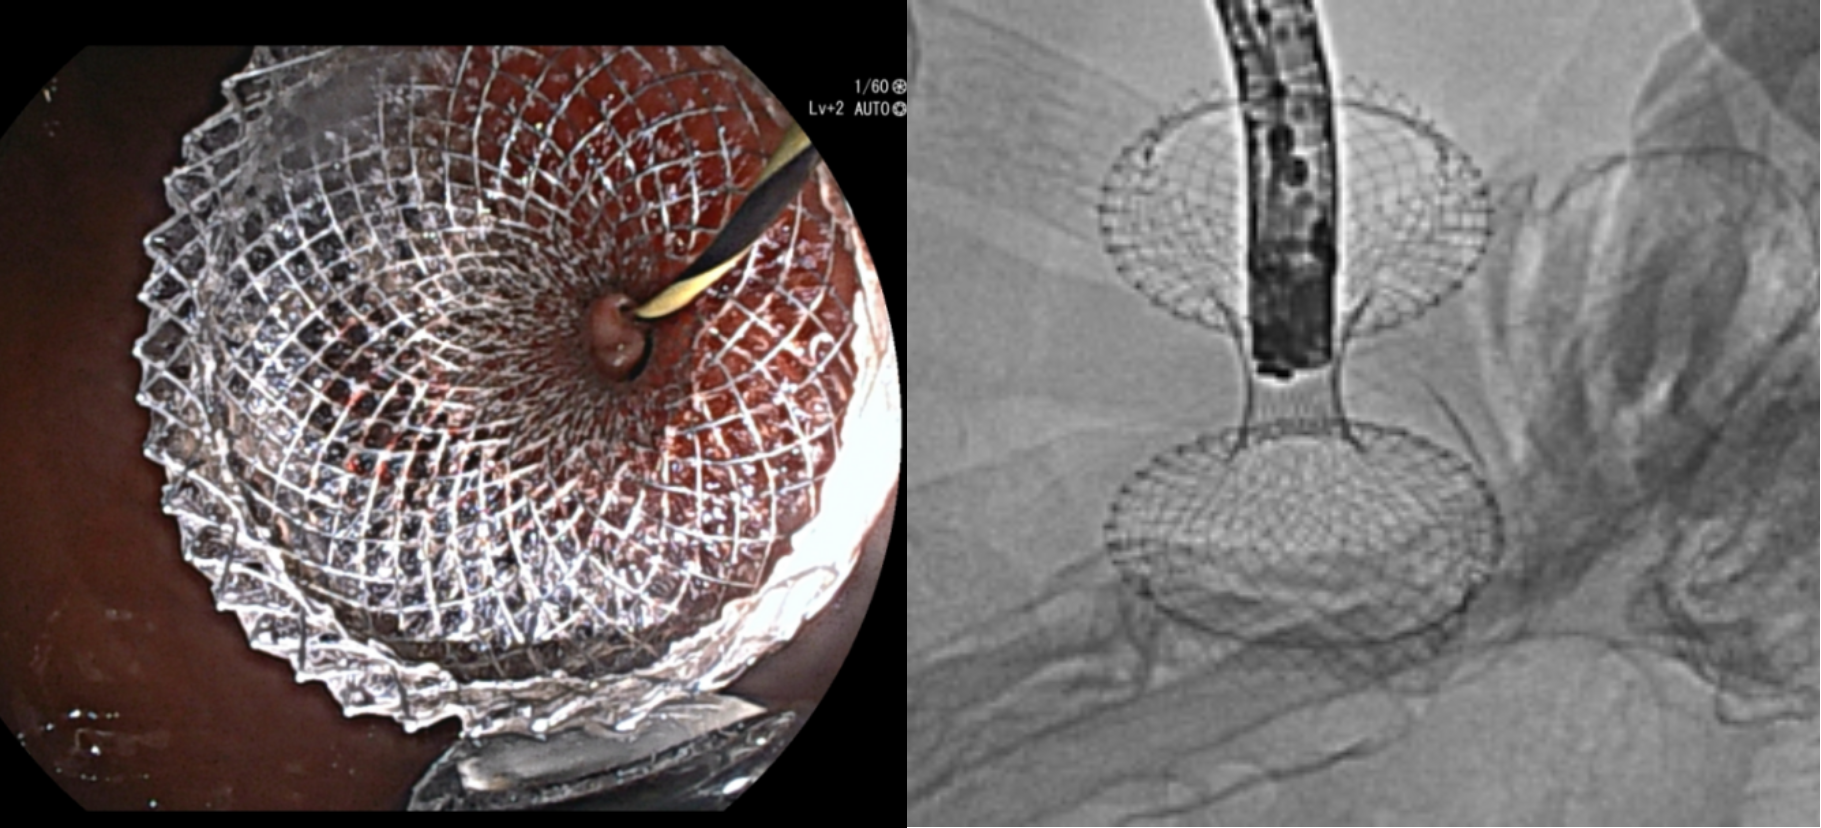

黄永辉在超声内镜实时引导下,采用19G穿刺针经胃体上段后壁穿刺目标肠腔,于肠腔内留置导丝。并通过特殊技术将导丝另一端带出口腔,形成胃-空肠闭环,固定目标肠段。在超声内镜及射线引导下,黄永辉成功置入10mm×2cm的双蘑菇头支架,实现胃-空肠的吻合。经支架胃腔端实时造影显示支架通畅,远端肠腔显影。患者术后恢复饮食,目前已顺利出院。

双蘑菇头支架释放成功——胃-肠之间建立新的进食通道

7a6bd7e790df71dbbb5e162eabcc618c~1.gif

经支架胃腔端实时造影显示支架通畅,远端肠腔显影(GIF动图)